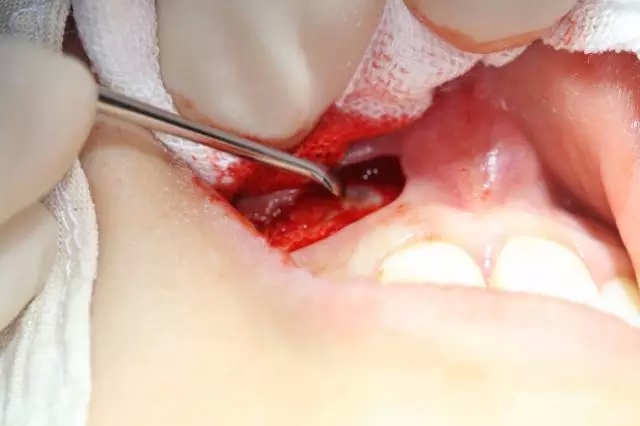

病例資料: 患者、柴xx、女、16歲。專科檢查及病歷如下圖: 患者同意我院正畸科建議,遂轉(zhuǎn)診倒外科。術(shù)前簽知情同意書。 治療過程: 圖1.術(shù)前的CBCT檢查:13阻生,疑為含牙囊腫。縱剖面顯示12牙根吸收至根尖1/3。 圖2.局部麻醉下 。行唇側(cè)弧形切口,12松動不到1°。 圖3.翻瓣、暴露骨面。 圖4.去骨、 暴露13牙冠 圖5.去骨、逐漸顯露13。 圖7.拔除13. 圖8.摘除囊壁 圖9.必須完整剝離囊壁。 圖10.摘除囊壁后形成的骨腔 圖11.超聲骨刀12根尖倒預(yù)備 圖13. 消毒棉球骨腔內(nèi)隔濕血液,紙尖干燥倒預(yù)備好的根管 圖14. 紙尖無血即可 圖15。MTA倒充填 圖16.骨腔填塞膠原蛋白海綿 圖17.拔除的13及摘除的囊壁 圖18.縫合 圖19.術(shù)后x線根尖片影像:MTA封閉根尖